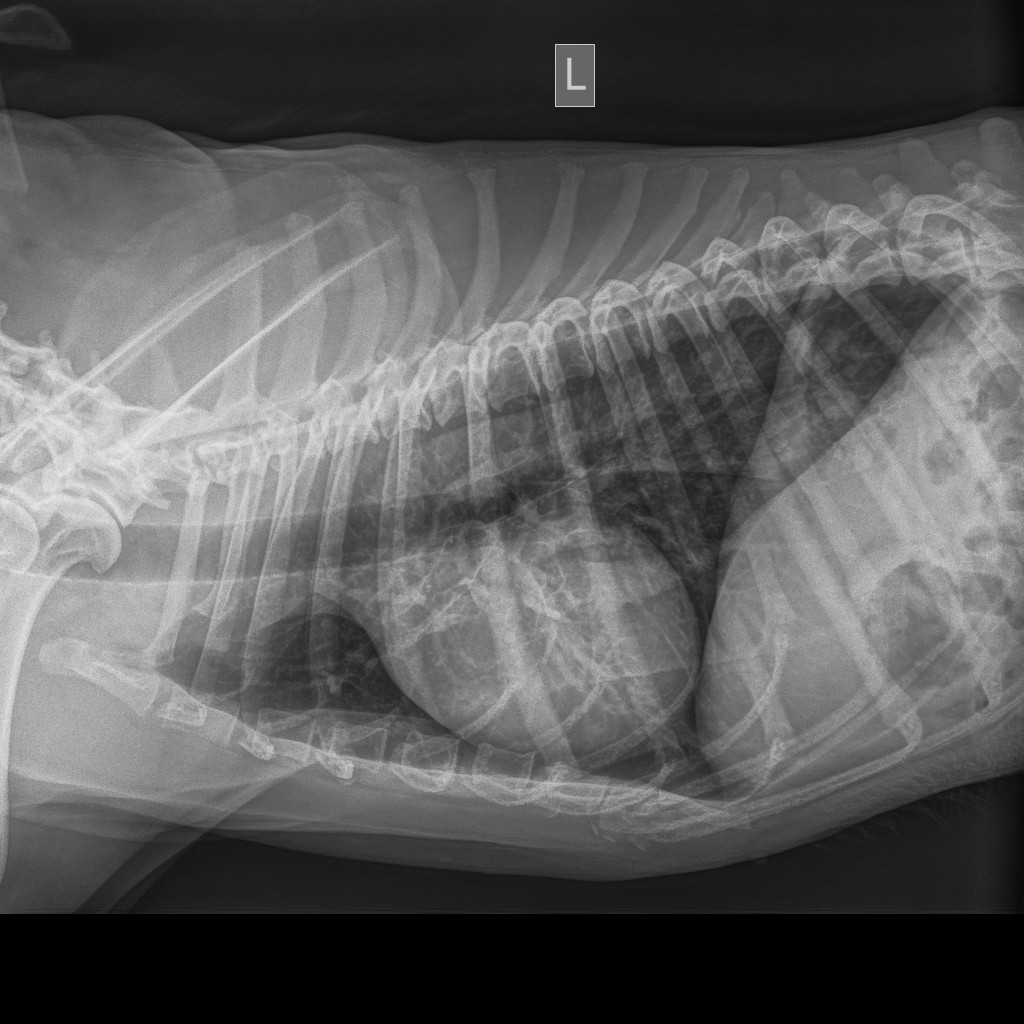

Сделали рентген лёгких.

На рентгене видны затемнение.

Возможны метастазы.